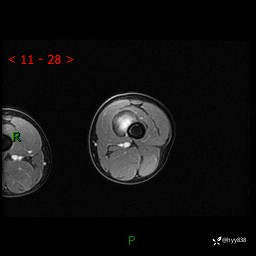

左大腿MRI平扫+增强